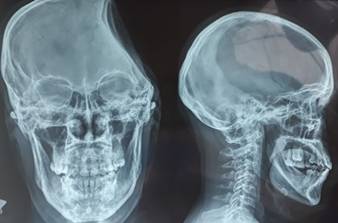

En las figuras 1, 2 y 3 se presentan neuroimágenes realizadas al paciente. (Figura 1)(Figura 2)(Figura 3)

Figura 3 En la placa craneal se puede observar el faltante óseo del hemisferio izquierdo, producto de la neurocirugía descompresiva.